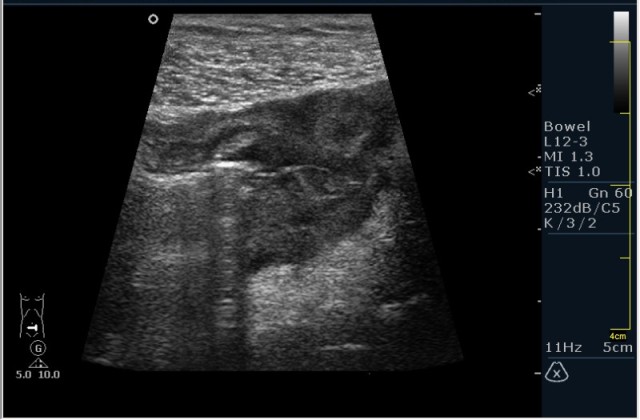

Пациент М. 60 лет с болями в левой подвздошной области. Пациент был направлен на УЗИ с диагнозом: левосторонняя почечная колика. Жалобы на боли в левой подвздошной области отдающие в таз. Анамнез без особонностей.

Пациента я сразу направил на эндоскопию. К сожалению, заключение было ожидаемым с моей стороны, опухоль (карцинома по результату биопсии).